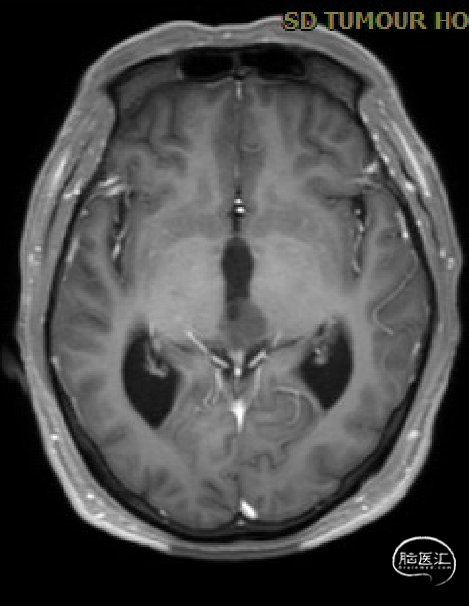

术前MRI与术后复查MRI对比

术后复查

术区无出血,脑室系统较术前显著缩小,脑积水缓解。